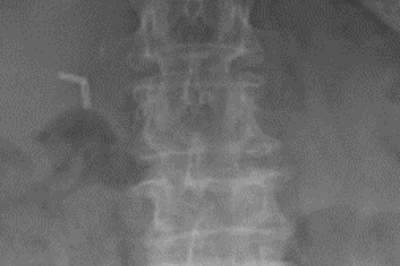

• Röntgenbild Wirbelfraktur

Röntgenbild Wirbelfraktur

Traumatische, craniale Berstungsfraktur mit Bandscheibenruptur